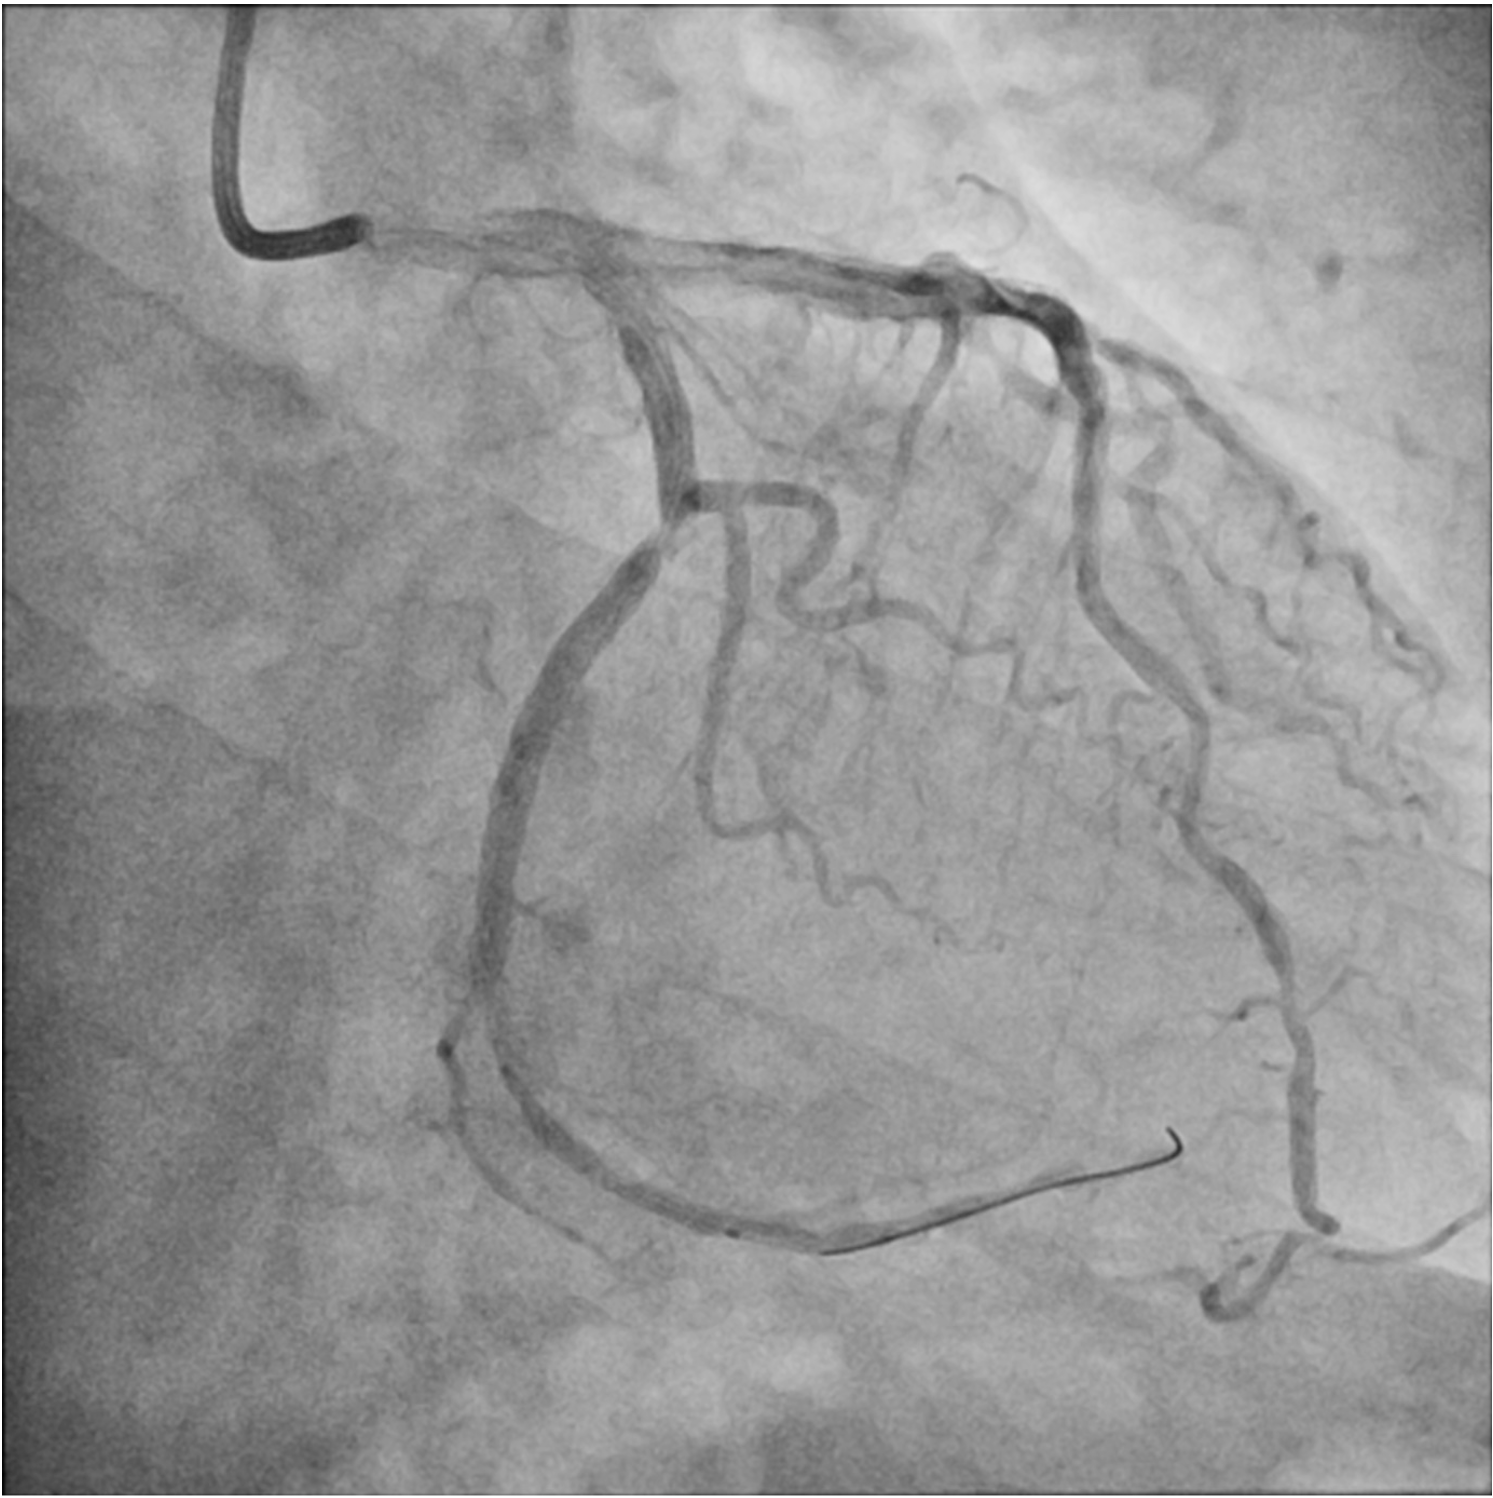

Distal small balloon retrieval was unsuccessful (Figure 1D). With the help of the Balloon-Assisted Guide-extension (BAG) system, the stent could be optimally positioned at the proximal LCX lesion by forward pushing with a 6-Fr Guideliner V3 catheter (Teleflex) and backward pulling by the small balloon (Figure 1E and F; Video). It was then deployed by sequential balloon dilatation with good expansion (Figure 1G and H). Another 2.5 x 24-mm DES was deployed at the distal LCX, which gave an excellent final angiographic result (Figure 1I and J).

Our case illustrates a novel repositioning system that can relocate and deploy a lost stent at an optimal site even in the absence of its original stent platform (Figure 2A-C). This can avoid wasting stents and serve as a viable bailout when conventional retrieval methods are unsuccessful.